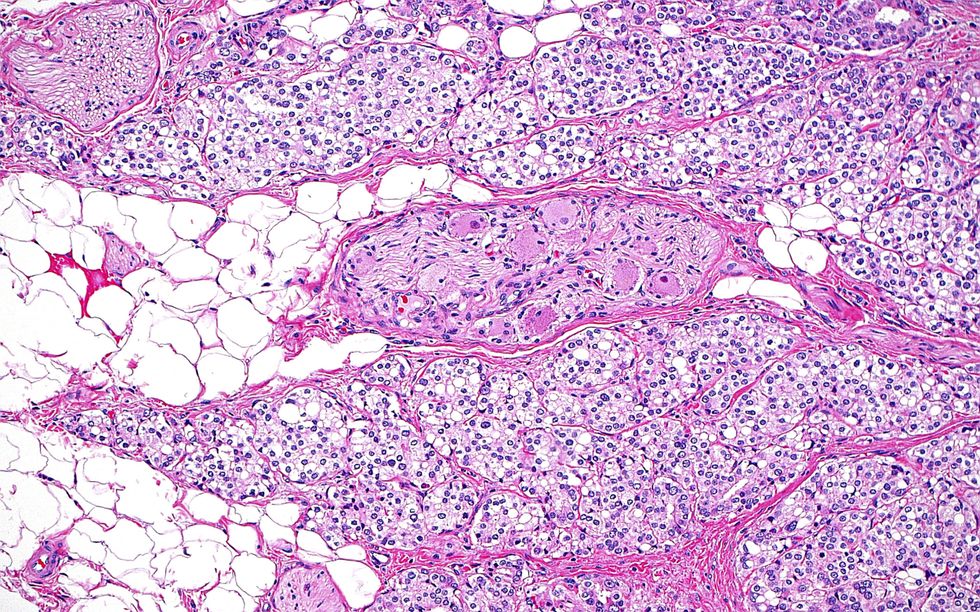

Prostate cancer has now taken over as the most commonly diagnosed cancer in the UK, pushing breast cancer into second place for the first time.

New figures from Prostate Cancer UK show that 64,425 men received a prostate cancer diagnosis in 2022. That's compared to 61,640 breast cancer cases during the same period.

It's a striking jump from the year before, when 51,823 men were told they had the disease – marking a 24 per cent rise in just 12 months.